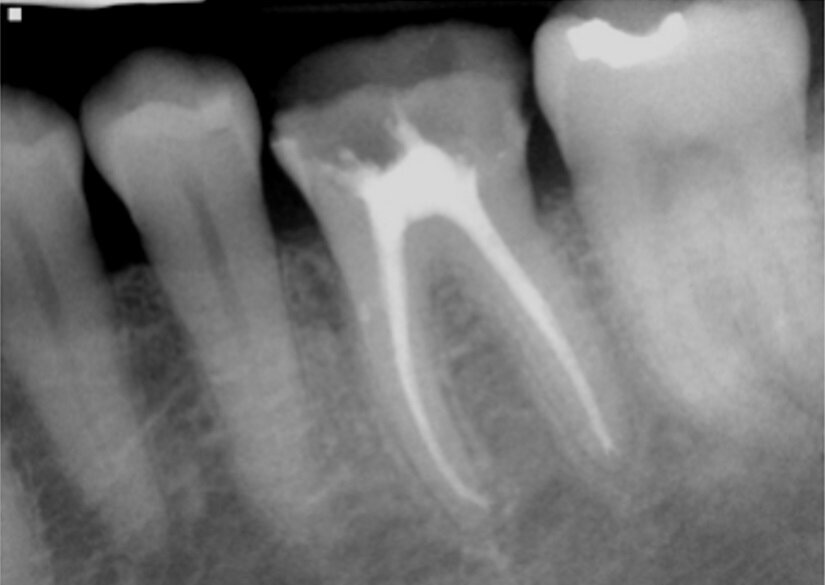

Fig. 15: Instrumentation performed with ExactTaperH DC files and obturation with a single cone of GP and Bioceramic Root Canal sealer completing endodontic treatment.

The teeth were isolated, and access performed with canal orifice identification. The SX file (ExactTaperH DC) was utilized to enlarge the canal orifice and aid in further file instrumentation. The canals were then instrumented to working length with the GP file. Each canal was instrumented with ExactTaperH DC files starting with the S1, then followed by the F1, F2 and F3 in the mesial-buccal and distal-buccal canals in both molars. The palatal canals in both teeth were competed with the F4 file. The canals were irrigated by alternating between sodium hypochlorite 3 percent (Vista Apex) and 17 percent EDTA solution (Vista Apex) during instrumentation and at completion. Canals were dried with paper points (ExactTaperH DC) matching the size of the final file used. Bioceramic Root Canal sealer (SS White) was mixed and dispensed on a pad. A gutta-percha cone (ExactTaperH DC) matching the final file size for each canal was coated with sealer and each canal was obturated in a single cone technique. The excess cones were cut off at the canal orifice and obturation was completed (Fig. 15). A temporary restoration was placed into both teeth using the GC Fuji Automix LC, and the patient was appointed to restore the two teeth.